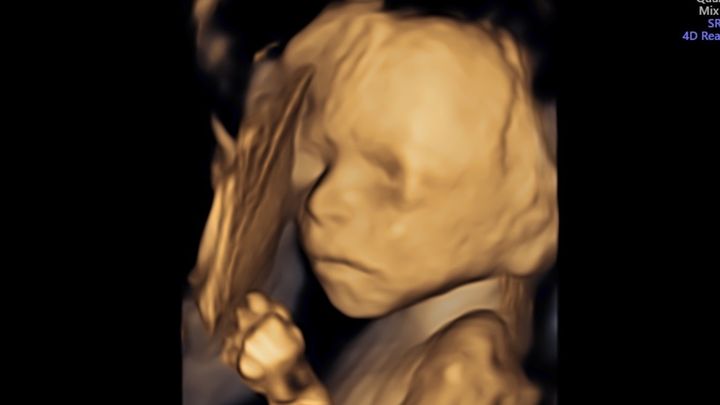

Hello everyone, my name is Haley. I am making this GoFundMe on behalf of my sister Sunny Forvilly and her husband Nick Forvilly. They recently found out that Baby Beau has a birth defect called Gastroschisis. Gastroschisis is a birth defect that causes the intestines to protrude from a hole in the abdomen, typically to the right of the umbilical cord. Occasionally, other organs are involved as well. This must be repaired surgically after birth, although surgery is not always possible immediately and depends on many factors including the amount of bowel outside of the body. While approximately 90% of affected infants survive in industrialized nations with proper medical care, there is still a 10% mortality rate due to complications or related defects and infections – even with the best medical care.